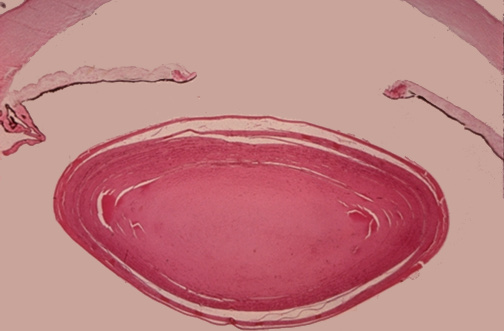

The normal crystalline lens of the eye is seen here at low power. The anterior chamber is above and the posterior chamber below.